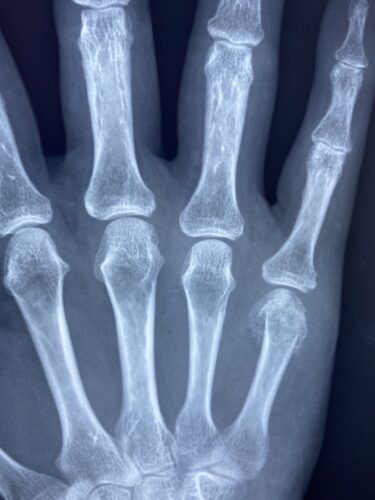

上肢の痛み・痺れ

牛久市で指の怪我(突き指・骨折・脱臼)にお悩みの方へ:症状の見分け方から…